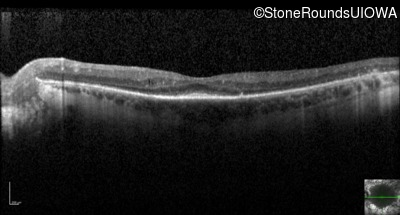

Optical Coherence Tomography - Right - 20/25 +1

Exemplar / OCT Stack

OCT Stack